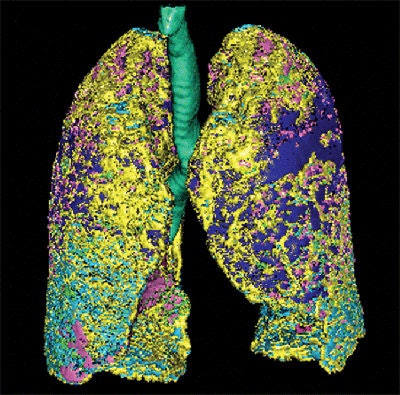

The lung volumes were examined on a computer-aided system that used CT attenuation values to distinguish fibrotic from normal, consolidated, and emphysematous regions on a PC. The automated tool extracts the lung from the CT images using a semiautomated threshold technique. Next, the bronchial trees and blood vessels are removed.

The algorithm categorized the lungs pixel by pixel, and then calculated the relative volume of each lesion to the CT lung volume as "normal(%)," "ground-glass opacities(%)," "consolidation(%)," "emphysema(%)," and "fibrosis(%)."